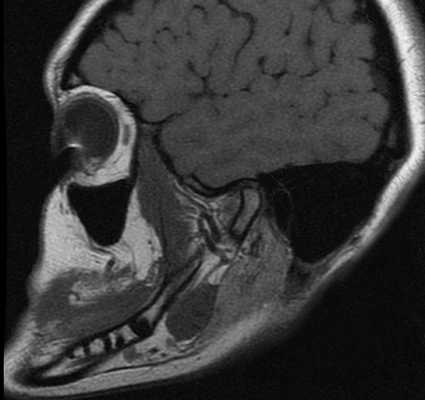

Снимок МРТ правого височно-челюстного сустава

Снимок МРТ височно-нижнечелюстного сустава